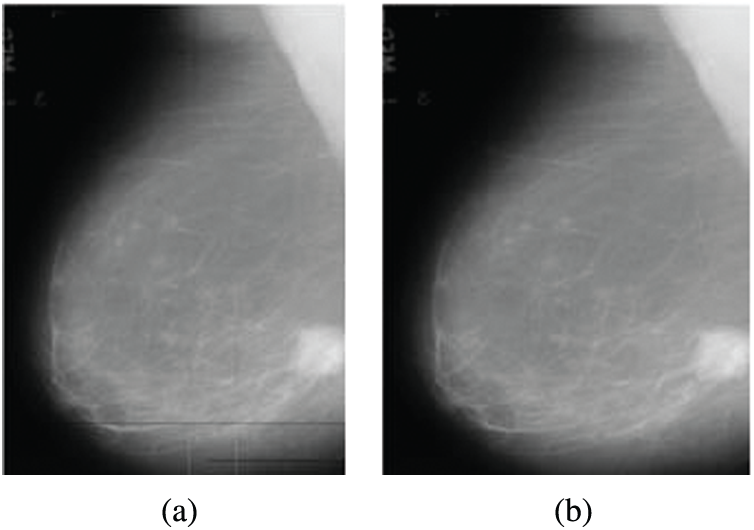

The noise results from digitization as horizontal and vertical lines in mammograms. This noise is removed using a 2D median filter. This filter is a non-linear digital filter. It is applied in a 3 × 3 neighborhood connection [19]. The median filter is used widely due to its efficiency as it removes noise and keeps edges. The median filter window is moved through the image, and each pixel value is replaced with the value of the median of pixels in its neighborhood. Fig. 2 illustrates an example of the removal of digitization line noise.

Figure 2: Digitization line noise removal from mammogram images (a) Original image with digitization line noise (b) Image after noise removal